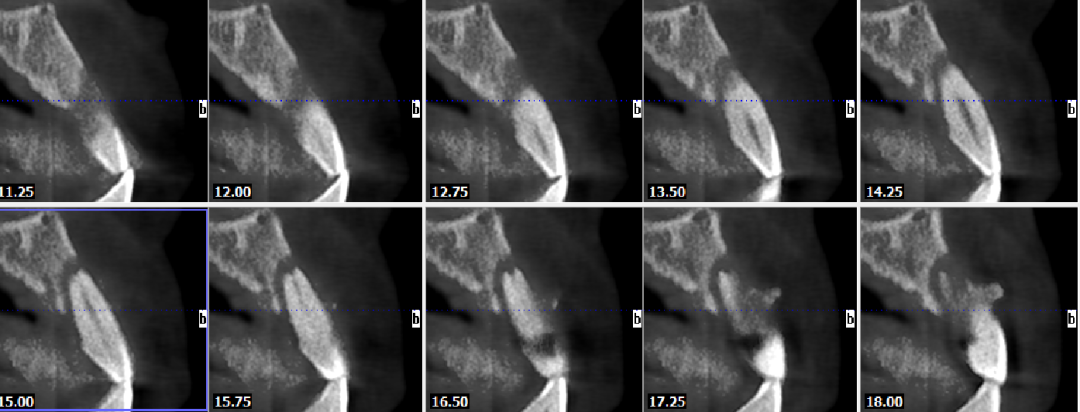

术前CBCT

21颊侧牙槽骨吸收至根尖,腭侧牙槽骨吸收至根尖1/3,根周可见低密度影。牙槽嵴宽度6.41mm。

局部反合、患牙长期牙周病变,骨质缺损,但软组织无明显缺失,为II类拔牙窝形态。

22冠状位CBCT情况

唇舌牙槽嵴宽度6.41mm,垂直骨缺失1/2,软组织无垂直向缺失。

术后4.5个月CBCT

术后即刻与术后4.5个月CBCT对比

可见种植体唇侧顶端有一定骨粉吸收,但仍在预期范围内。